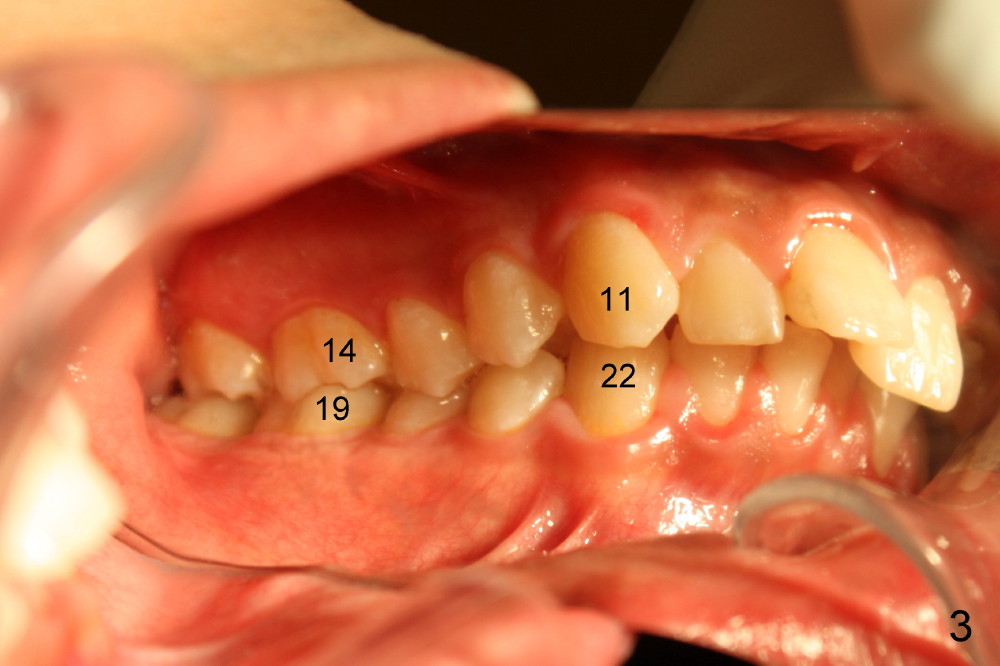

A 21-year-old man has severe maxillary protrusion (Class II malocclusion) with crown fracture of #7 (Fig.1,2,3 (latter two mirror images). Treatment plan is to place pre-fabricated post and provisional for #7 (Fig.4,5 C) and start ortho treatment with extraction of upper 1st bicuspids (Fig.5 *, <). When ortho finishes, fabricate full-coverage porcelain crown for #7.

The patient returns 1 month post distalization of the upper incisors (Fig.10-12, 9 months of treatment). Bilateral canine relationship is Class I (Fig.11,12). All needs to be done is to continue distalizing the upper incisors or slightly mesialize the canines if indicated.